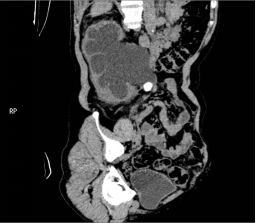

入院后,三维CT发现患者双侧输尿管结石,右肾盂输尿管连接处狭窄,右肾严重积水,左肾也因结石梗阻导致肾盂输尿管积水。肌酐1284.5μmoI/L,已经达到急性肾功能不全(尿毒症期)。王春阳教授立即为患者进行超声引导下右肾穿刺造瘘,改善患者肾功能,并制定拟行达芬奇手术机器人辅助腹腔镜下双侧输尿管切开取石术+达芬奇手术机器人辅助腹腔镜下右侧肾盂成型肾盂输尿管再吻合术,决定一次手术解决目前导致患者肾脏积水的全部问题。

王春阳教授介绍,仅利用一次手术同时处理患者全部问题,大大增加手术难度,但能减轻患者的痛苦和费用。对于结石大、梗阻明显、结石坎顿的病人,为及时解决梗阻,挽救肾功能,可选择输尿管切开取石。传统的输尿管切开取石手术疗效可靠,但患者手术创伤大,恢复慢,住院时间长。运用达芬奇手术机器人辅助腹腔镜下行输尿管切开取石术不切断肌肉,不损伤较大血管神经,手术直视下进行,术野可放大10倍,手术损伤小,出血少,恢复快。同时该病人CT中表现出右侧肾盂输尿管连接部狭窄,切开取石后行右侧肾盂成形术,去除狭窄段,对肾盂输尿管连接部重新塑形,显著解除梗阻。